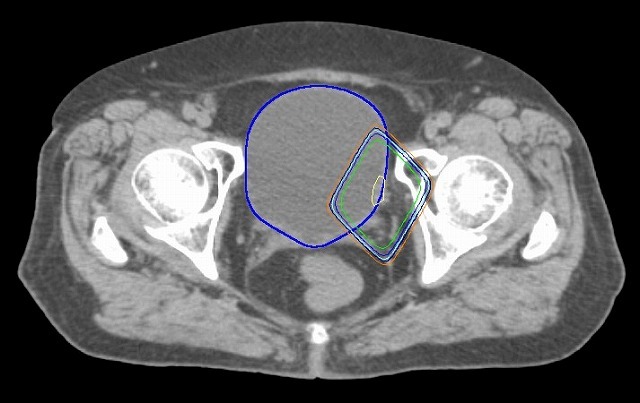

骨盤内のリンパ節に転移のある場合は前立腺に加えてリンパ節領域も同時に照射。